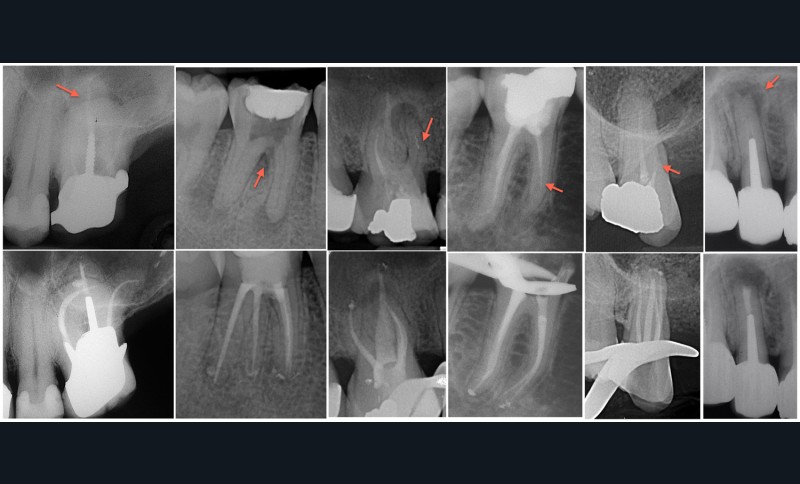

La décision est prise selon le contexte clinique et les attentes du patient. L’étanchéité coronaire est évaluée, même si son appréciation reste subjective. De même, le projet prothétique futur entre en jeu. L’accès au réseau endodontique sera plus ou moins facile. Il est d’ailleurs tout à fait possible d’envisager un passage à travers l’élément prothétique. L’anatomie canalaire complexe et la présence d’obstacles (fragments, calcifications…) peuvent être des indications d’abord chirurgical.

La chirurgie endodontique ne se limite pas à couper la racine mais consiste en un traitement endodontiquea retro. Comme pour le retraitement par voie orthograde, l’intervention peut intéresser un ou plusieurs canaux. L’imagerie est l’élément clé de la décision. Le CBCT (Cone Beam Computed Tomography) vient au service du sens clinique du praticien.